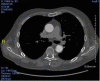

This report outlines a case of atypical presentation of COVID-19 viral infection. A two-stage repair of a Crawford type III thoracoabdominal aortic aneurysm was planned for a 65-year-old man. The first stage, thoracic endovascular aortic repair in the descending aorta, was uneventful, and the patient was discharged on postoperative day 2. He was readmitted 10 days later, presenting with diarrhea, lower limb pain, and weakness after walking 25 meters. The patient displayed no fever or upper respiratory tract signs or symptoms. Findings on computed tomography and magnetic resonance of the spinal cord were normal. The patient tested positive for COVID-19 virus and later during hospitalization developed more typical fever and respiratory symptoms that were managed medically.